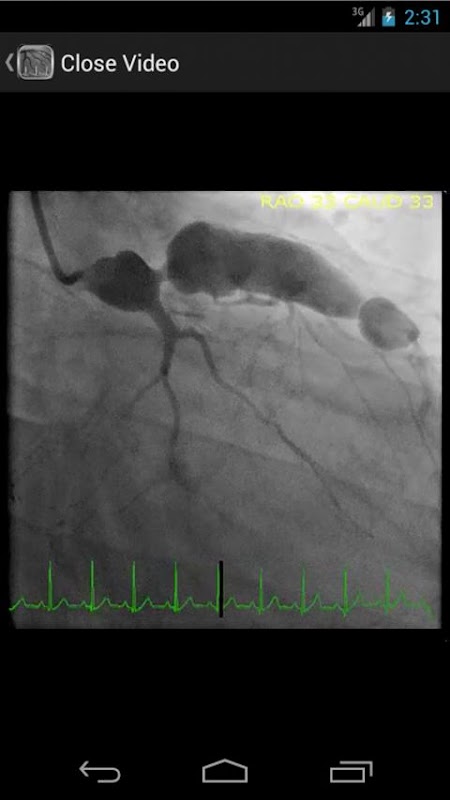

* Добавлена база данных, содержащая более 30 видео (коронарной ангиографии, ventriculograms и aortograms) обоих распространенных и редких находок в лаборатории катетеризации сердца